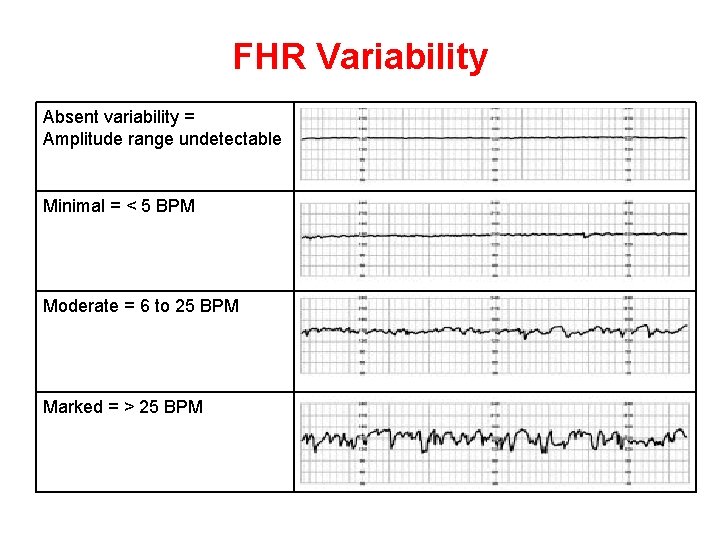

Baseline variability The minor fluctuations in baseline FHR occuring at three to five cycles per minute. It is measured by estimating the difference in beats per minute between the highest peak and lowest trough of fluctuation in a one-minute segment of the trace.

FHR Variability Absent variability = Amplitude range undetectable Minimal = < 5 BPM Moderate = 6 to 25 BPM Marked = > 25 BPM